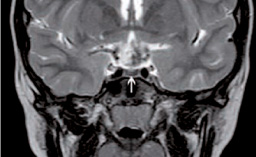

«Hypothalamite» : nouvelle maladie auto-immune ?

Les auteurs décrivent une femme de 35 ans présentant une masse suprasellaire croissante, une sella partiellement vide, un diabète insipide central, un hypopituitarisme et une hyperprolactinémie…